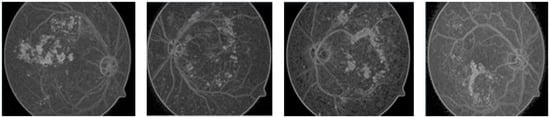

The new scheme avoids domain-specific problems, as fixed dimensions can be useless/not fit for all images, especially images with micro textures like bio medical images, where abnormalities are not observed in some regular shapes but can be seen when drawing irregular polygons with different dimensions. Thus, we can expect calculations to be more accurate because they cover the maximum amounts of interested/abnormal regions (in case of medical images) accordingly. The main advantage of this scheme over a scheme with regular polygons is the segmentation of a fewer possible and more specific homogeneous number of seeds with minimum noise, as shown in Figure 4.

By using the regular polygonal seed selection methodology for bio-medical, images like retinal fundus images slices are not connected, which results in extreme difficulty for useful segmentation [24]. However, an irregular polygonal seed selection scheme resolves this issue because it allows for any possible sizes, dimensions, and shapes to be considered as regions of interest (ROI). At the post processing stage, a K-mean algorithm [25,26] is employed on improved segmented regions, which results in the removal of noise for improved results.

On the other hand, the proposed scheme uses marker-based segmentation approach radii, shapes, and centers of the irregular polygon-defined foreground, which improves segmentation results. The K-mean segmentation results are disturbed when K > 12 (K = 12; maximum threshold value) on retinal fundus images with the proposed seed-based segmentation scheme, which can successfully produce more useful clustering information compared to information produced by applying previous schemes, as shown in Figure 4.

Figure 4. Irregular polygonal seed-based improved region growing outcome using K-mean clustering.

Entropy 22 00567 g004

Figure 5. DR segmentation based on the watershed technique.

Entropy 22 00567 g005